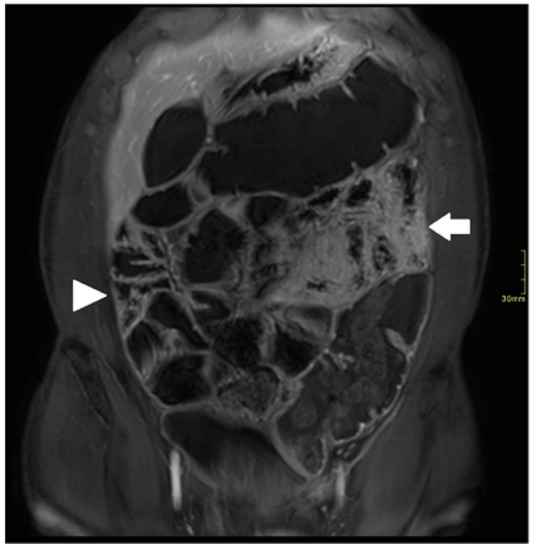

3. Motion Artifact

5. Bowel Distention